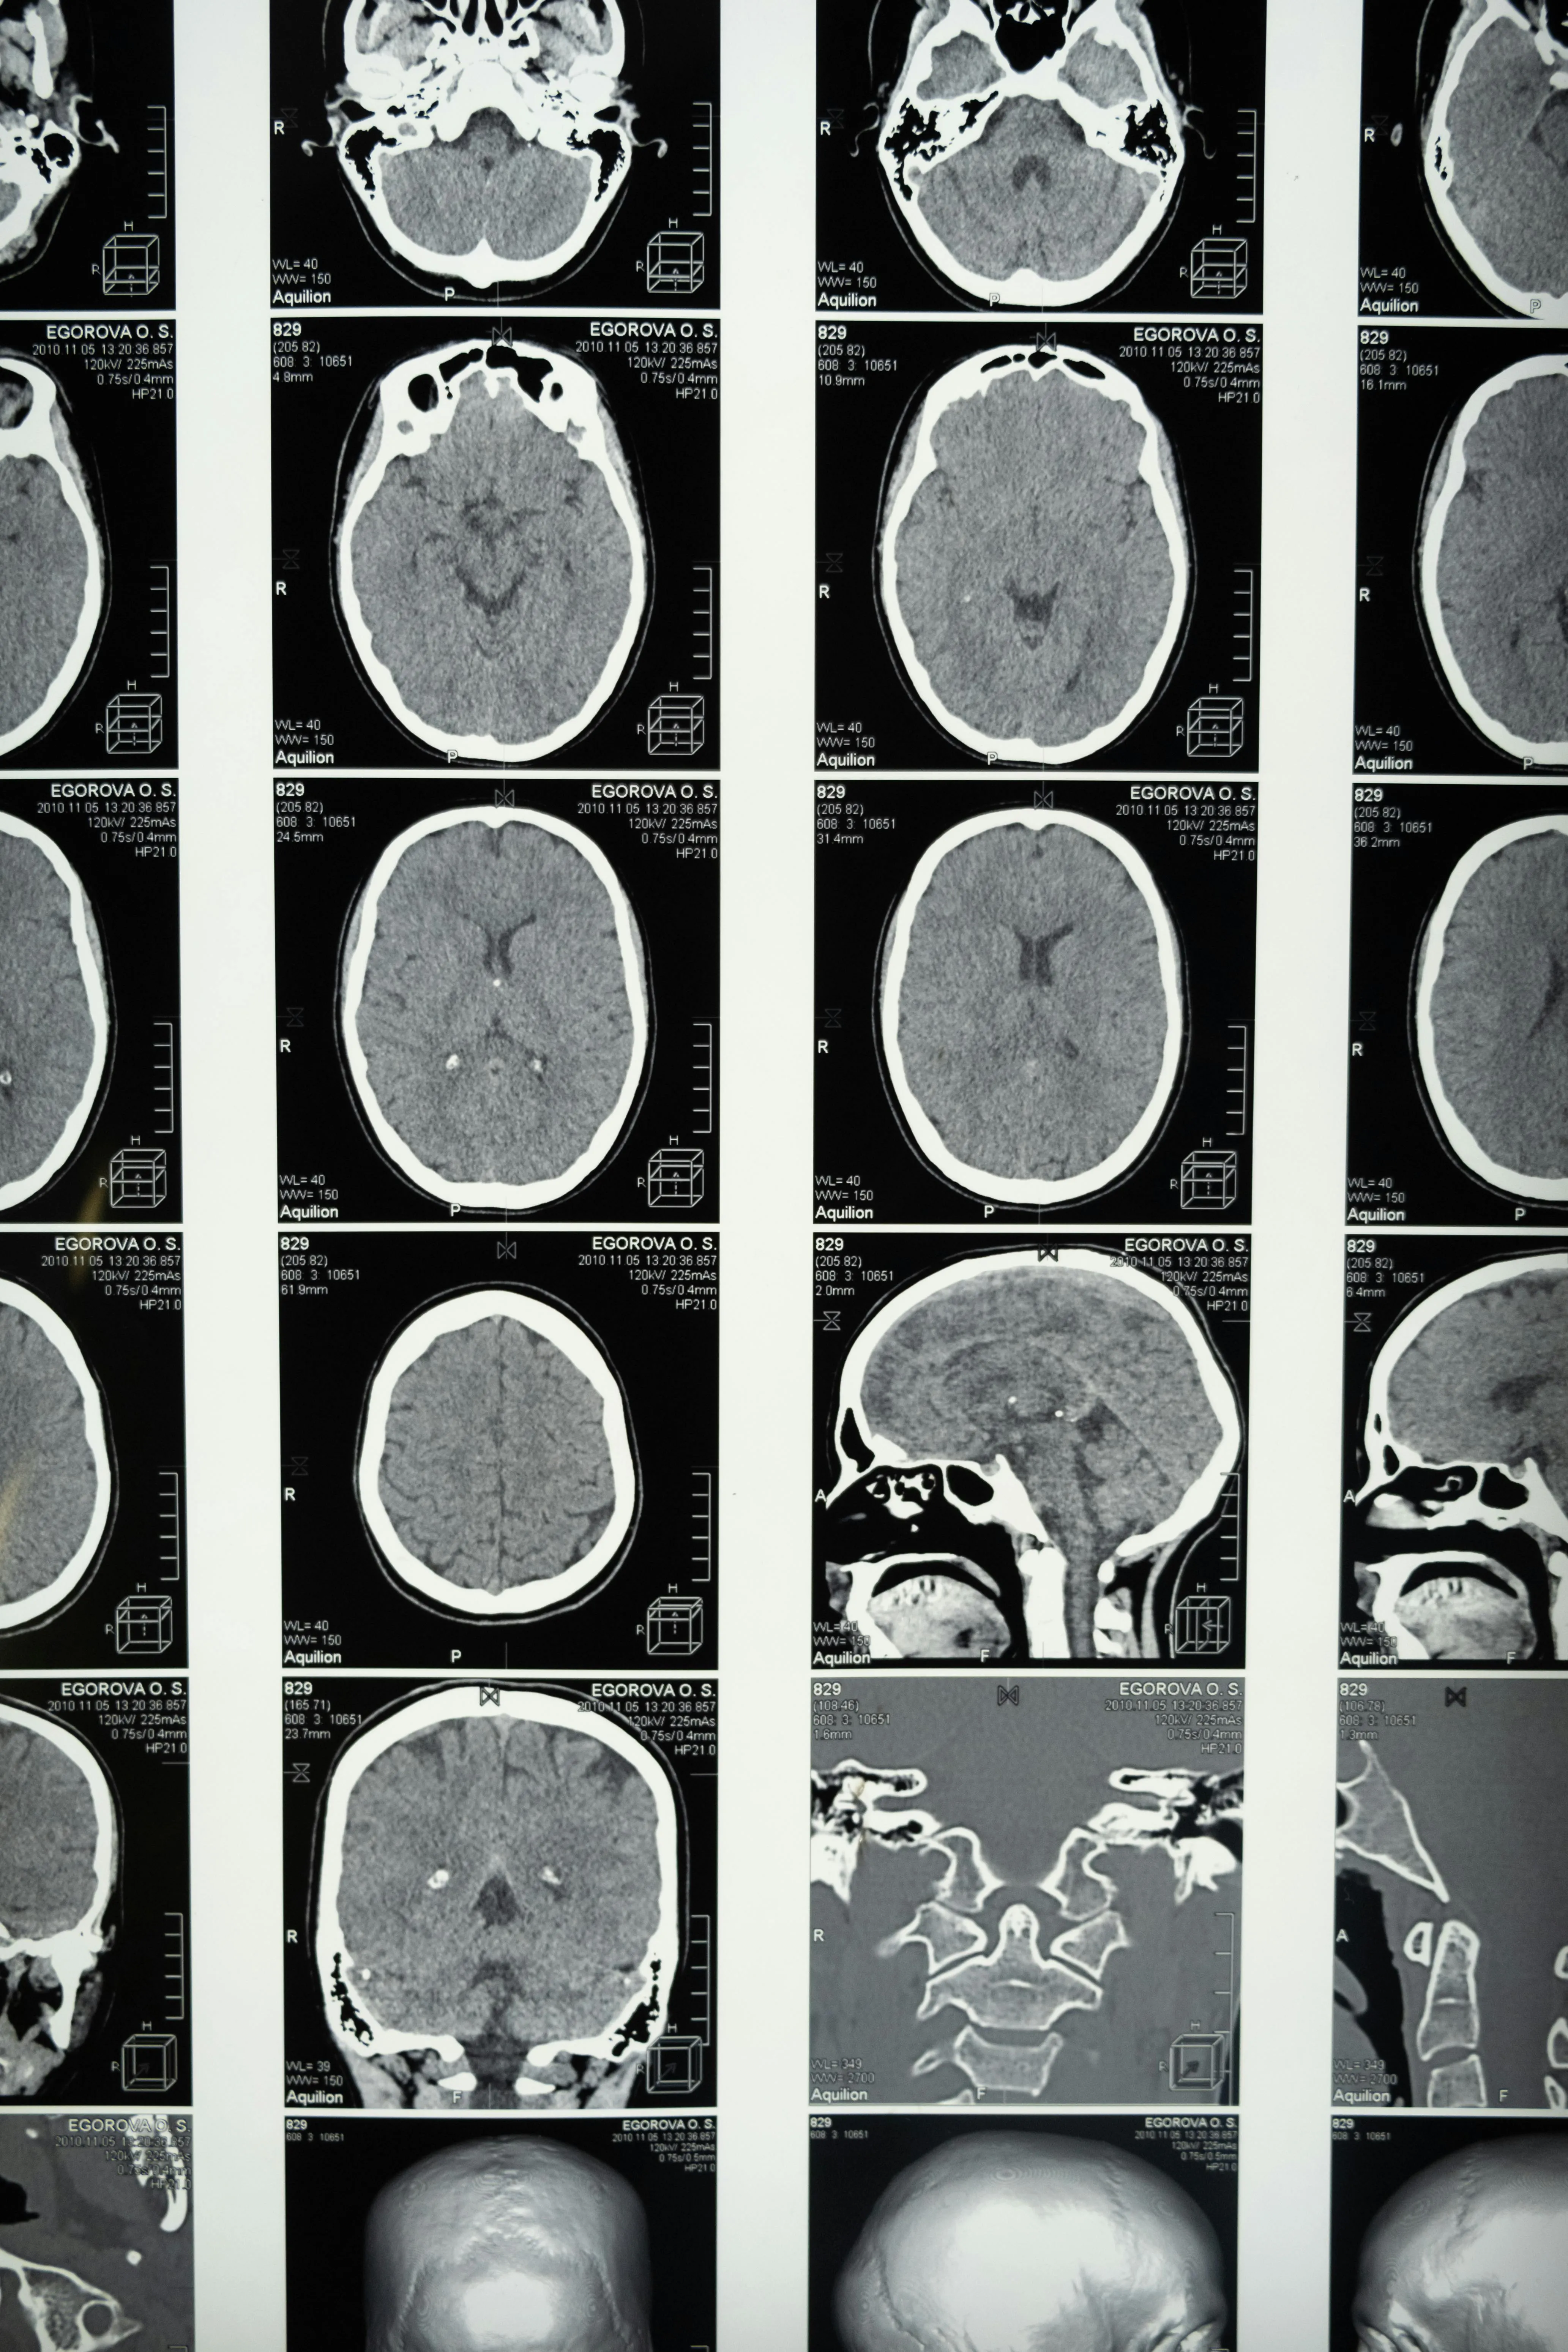

우리나라에서 흔히 발생하는 뇌혈관 질환 중 하나가 바로 뇌경색입니다. 뇌경색은 뇌혈관이 막히면서 혈액 공급이 원활하지 않아 뇌세포가 손상되는 질환인데요. 중요한 점은 뇌경색 초기증상을 빨리 발견하느냐에 따라 후유증과 생존율이 크게 달라진다는 것입니다. 오늘은 많은 분들이 궁금해하는 뇌경색 초기증상과 대처 방법에 대해 자세히 알아보겠습니다. 지금 알려드리는 대처법은 혼자 알고 있어도 되지만 주변 가족분들이 알고 있으면 더 좋겠죠?

뇌경색은 발병 직후 몇 시간 내에 치료를 시작해야 뇌 손상을 최소화할 수 있습니다. 뇌경색 초기증상을 놓치면 치료 골든타임을 놓쳐 반신마비, 언어장애, 기억력 저하와 같은 심각한 후유증이 남을 수 있습니다. 따라서 작은 변화라도 놓치지 않고 즉시 병원을 찾는 것이 생명을 지키는 길입니다.